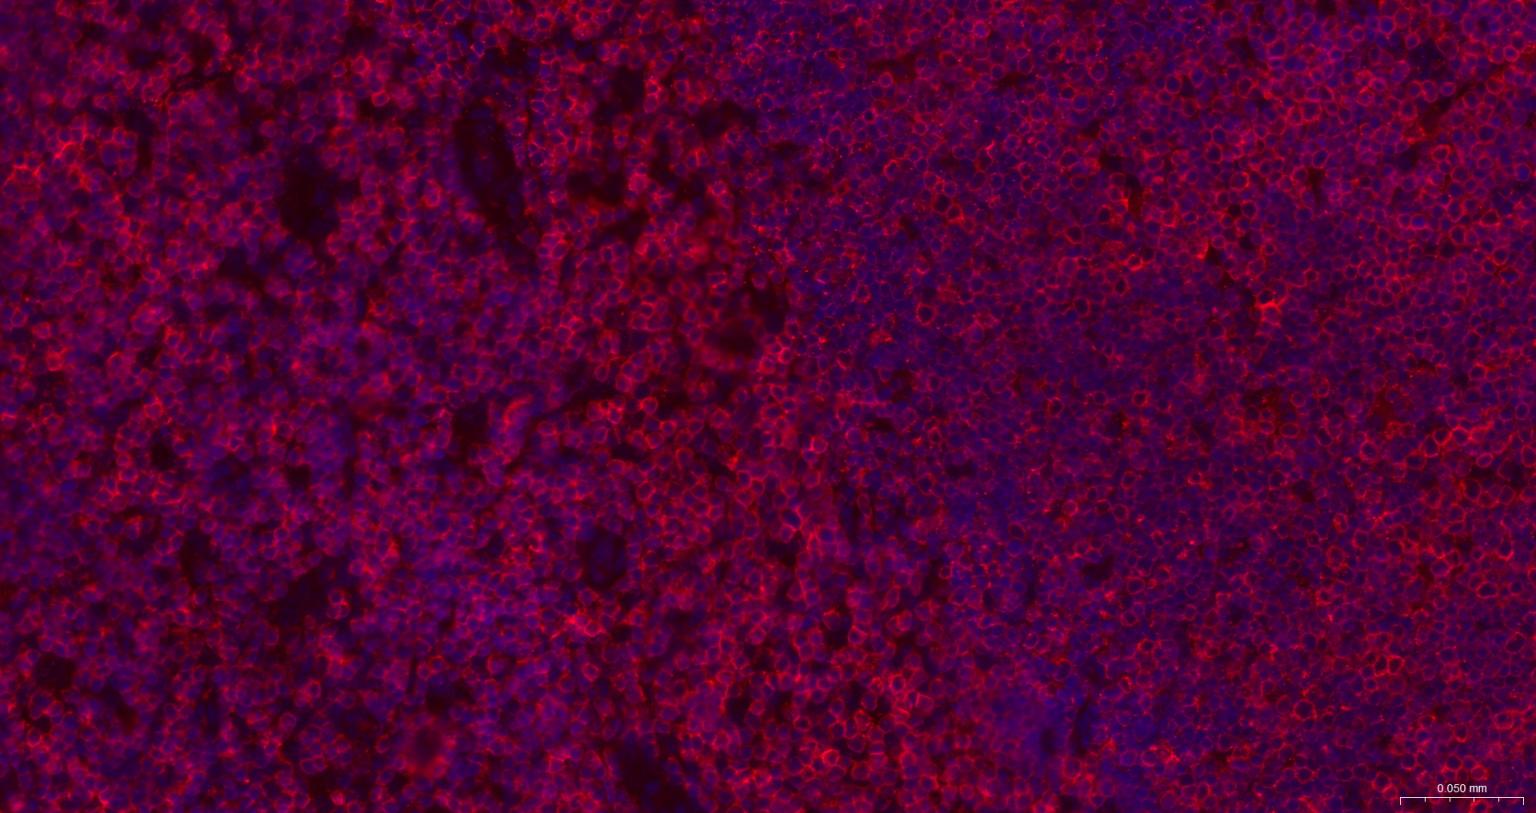

IFHuman, Mouse, Rat1:500-2000